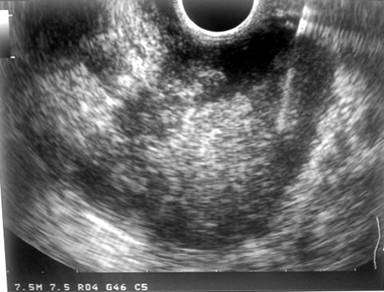

Endoscopic retrograde cholangiopancreatography (ERCP) for the patient was done and CBD stent used. In continue we did EUS-FNA (Figure 5) and there was a mixed echoic lesion adhered to head of pancreas with invasion to portal vein, SMA (superior mesenteric artery) and SMV.

Figure 5. EUS-FNA indicated echoic lesion adhered to head of pancreas with invasion to portal vein, SMA and SMV. |